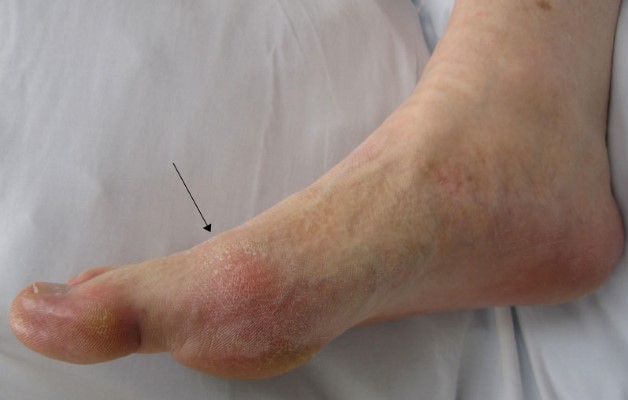

- отеки пораженной стопы;

Если артроз ярко выражен и сопровождается воспалением суставной сумки, у человека может подняться температура. Больная стопа и пальцы ног опухают, краснеют. становятся горячими на ощупь.

Пациенту также придется сдать анализ крови, чтобы исключить артрит. Ниже на фото представлен артроз первой степени и последующие стадии развития заболевания.